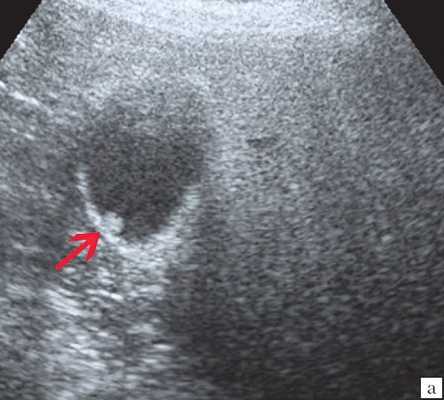

- Ультразвуковая диагностика. К визуализирующим методам диагностики холангита относятся УЗИ брюшной полости и печени, ультрасонография желчных путей. С их помощью удается получить изображение желчных протоков, выявить их расширение, определить наличие структурных и очаговых изменений в печени.

Ультрасонография является эффективным средством выявления полиповидной формы холестероза 8. Традиционной считается следующая сонографическая характеристика холестериновых полипов: неподвижные гиперэхогенные структуры, которые не дают акустической тени и прикрепляются к стенке желчного пузыря. Контуры таких образований, как правило, ровные, а размеры таких образований различны, чаще не превышают 10 мм (рис. 2).

Клиническая картина желчнокаменной болезни многообразна [5-6, 10]. Условно выделяют хроническую болевую, хроническую рецидивирующую, диспептическую, стенокардитическую и ряд других клинических форм. Характерным ультразвуковым признаком конкремента в желчном пузыре является его акустическая тень. Такая тень возникает из-за высокой плотности камня по сравнению с мягкими тканями. Наличие или отсутствие тени помогает отличить камень от полипа желчного пузыря (рис. 4).